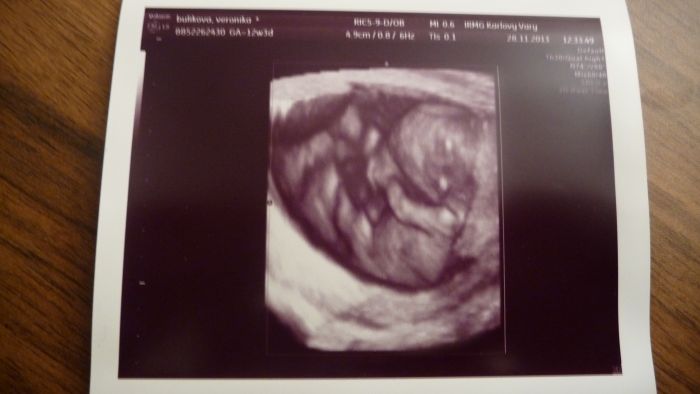

Ahojte těhulky, tak jsem dnes byla na screeningu, KONEČNĚ... ALE... čekám prý flegmatické spací mimčo

Doktor do mě bušil, musel mě vyšetřit vaginálně a mímo pořád spinkalo, vždy se jen zavrtělo, jako že nech mě a zase spinkalo. Vypadá prý vše ok, krev budou volat jen pokud něco objeví. Tak snad to bude také OK. Jinak máme 4,64 cm a Dr. mi řekl, že nejspíš nebudu v tom 12tt ale asi v 10tt. Tak nevím. Posune se mi TP, tak příští pondělí jdu na kontrolu k mé Dr. tak písnu. Srdíčko jsme s přítelem slyšeli a bylo to úžasné. Pohlaví nevíme, prý se nám správně nenatočila a je ještě brzy. Ale dva známí tatínkové na to koukali a bylo jim hned jasno. Viděli holčičku.

Tak snad se chlapáci taťáci nemýlili. Přítel byl na screen. celou dobu semnou a byl nadšený, nejvííc ze zvuku srdíčka. Mám 4 fotky a to jen proto, že to malé jen spalo, tak ho Dr. aspoň fotil. Bylo nádherné vidět toho tvorečka, jak si dává ručičky k obličeji a za hlavu. Jednu nožičku mělo nataženou a druhou pokrčenou. Jsem šťastná. Gratuluji maminám co ví už pohlaví.